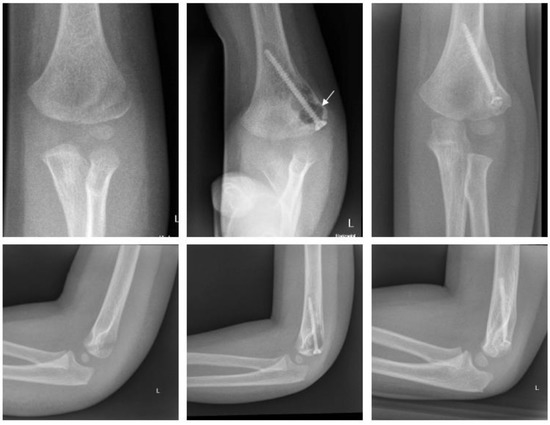

2.4.2. Fracture of the Medial Epicondyle